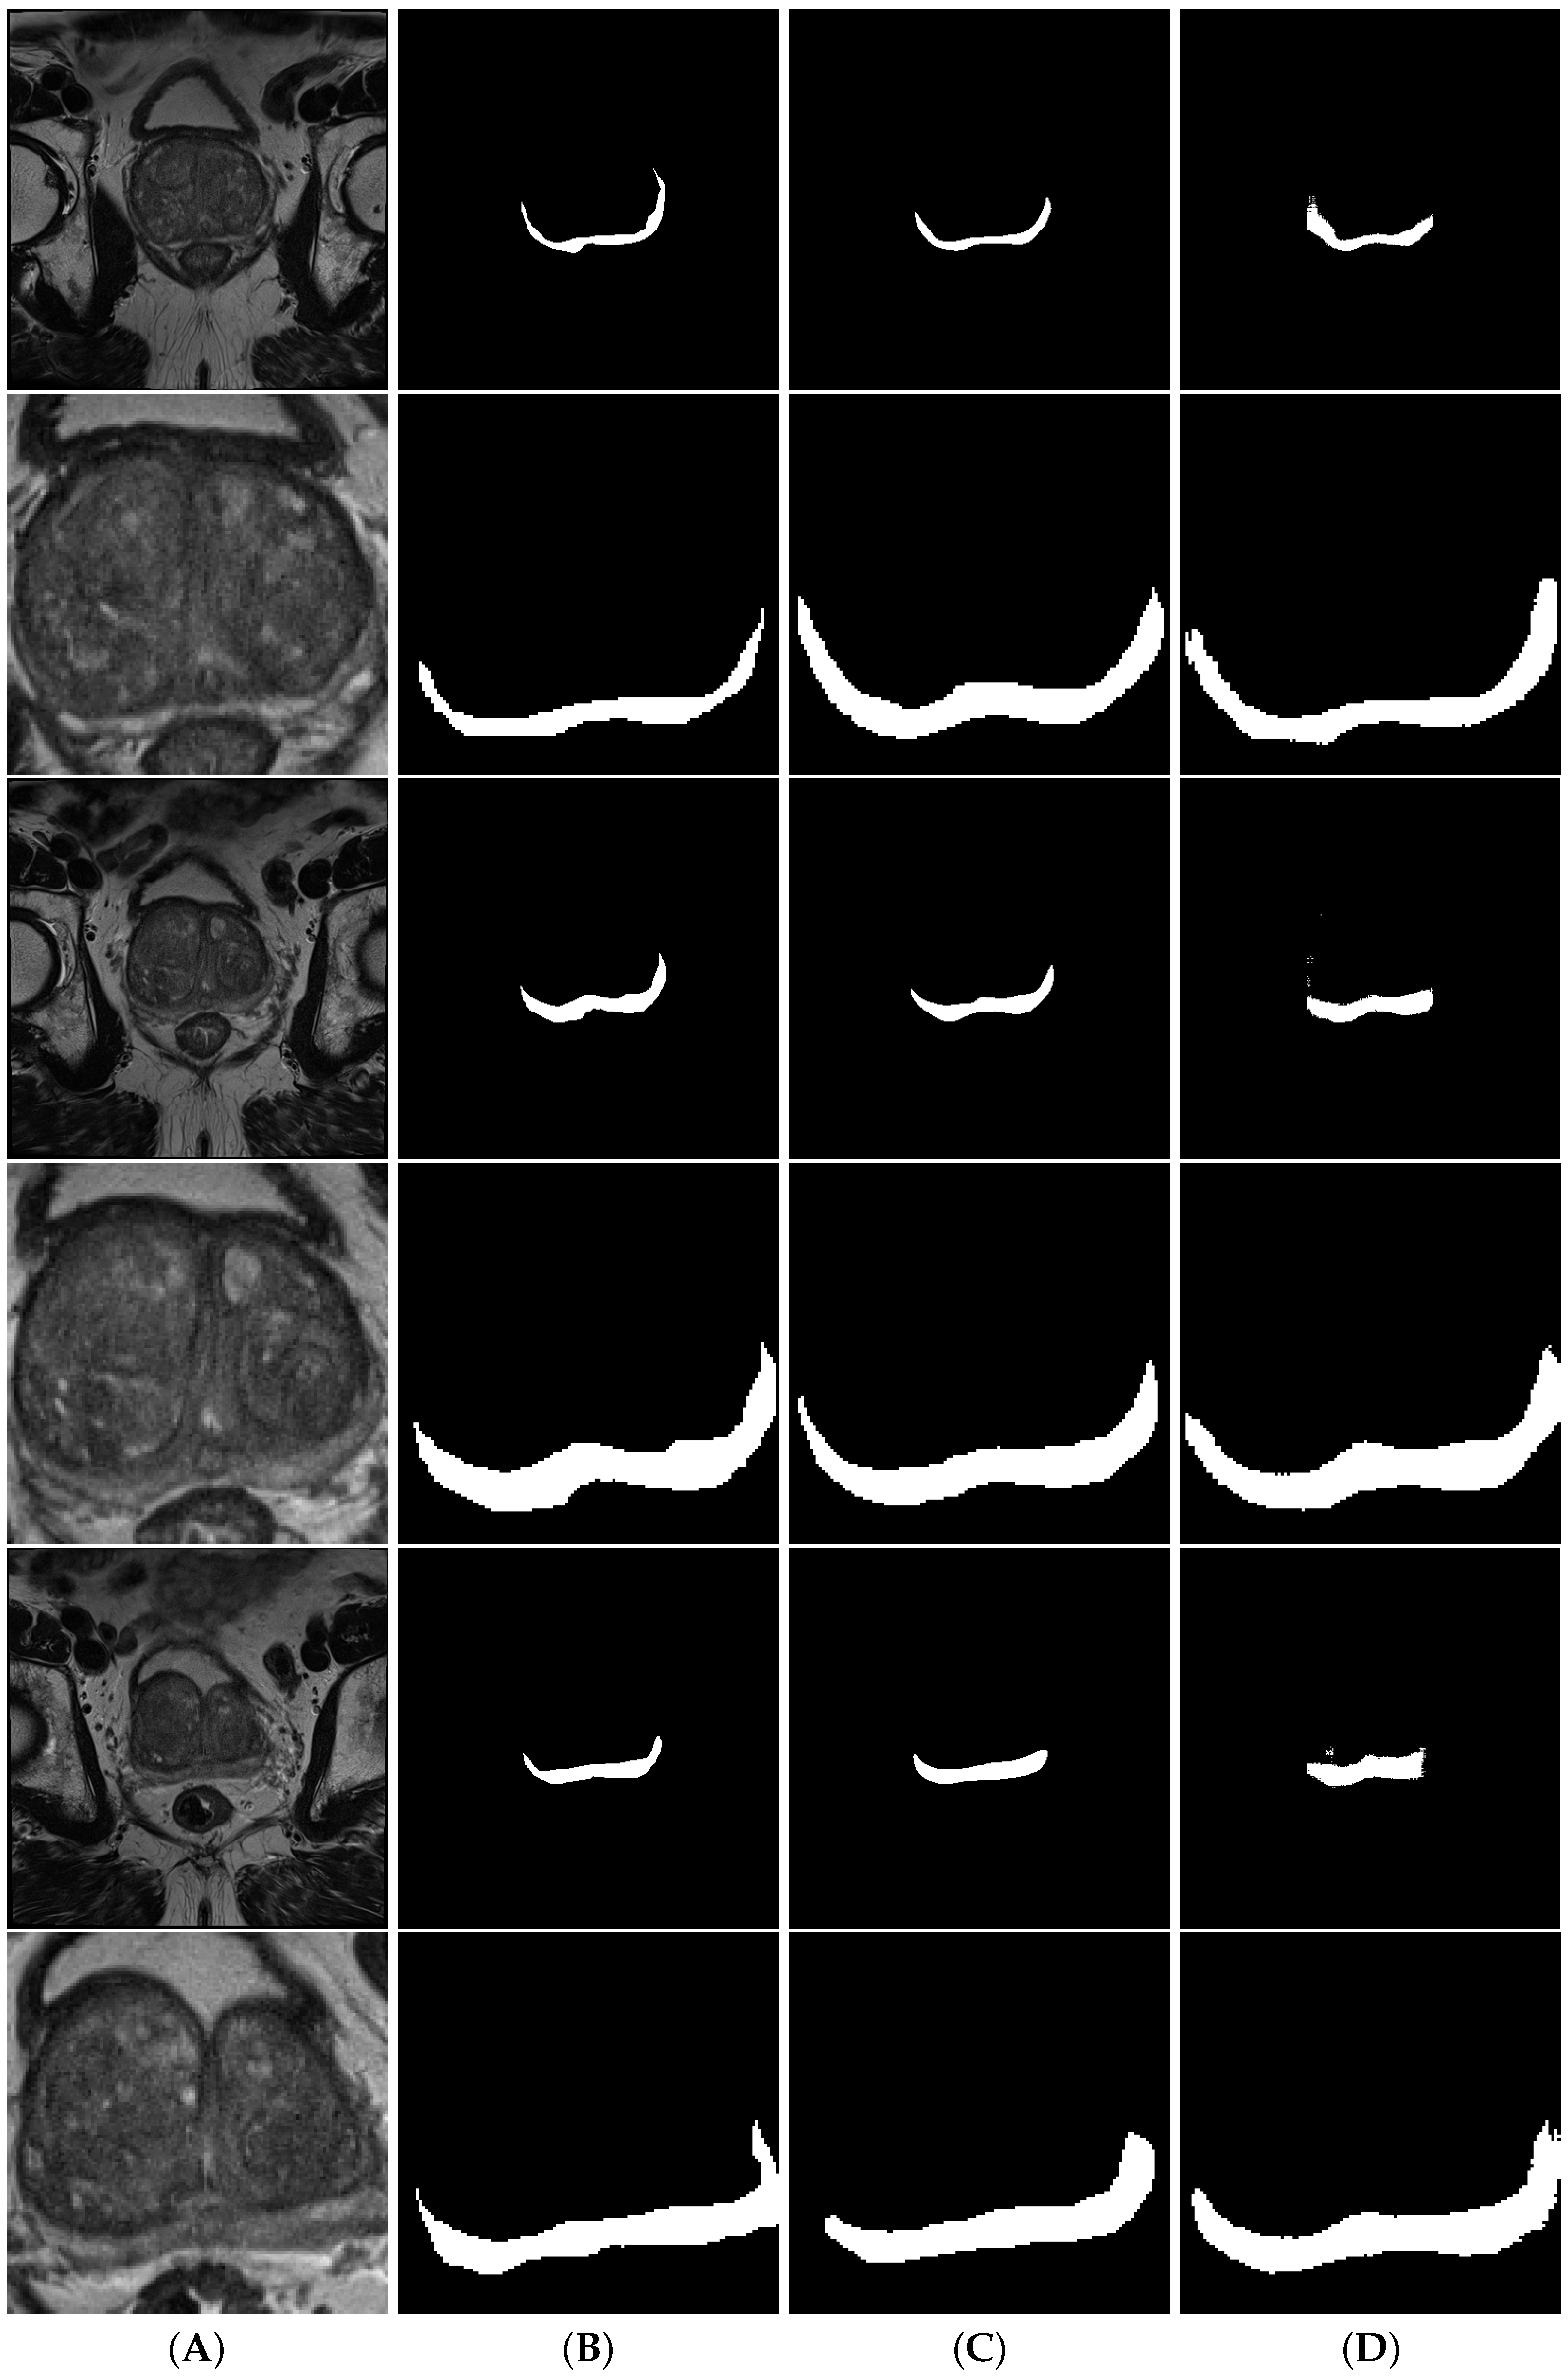

3.3. Zone Segmentation